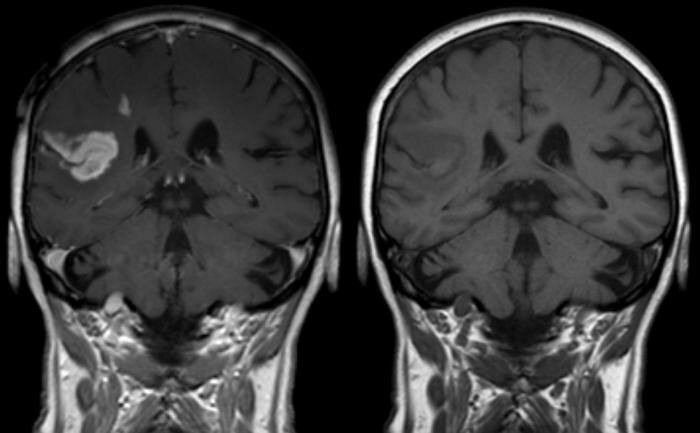

Заболевание под названием ОНМК, расшифровывается как острые нарушения мозгового кровообращения. Другими словами, более простыми для обычного пациента – это проявление инсульта. Это серьезное заболевание, которое может закончиться летальным исходом, если не соблюдать все рекомендации врача. Чем же страшна эта болезнь? Дело в том, что во время инсульта, происходит повреждение, а затем отмирание клеток головного мозга. Это вряд ли может говорить о чем-то хорошем, ведь целостность человеческого организма зависит от каждого его элемента. Причиной для нарушения целостности и отмирания клеток служит появление тромба в кровеносных сосудах головного мозга. Не только сам тромб, но и разрыв сосудов, обернется неблагоприятным эффектом. Такого рода блокировка вызывает гибель нервных клеток, а также клеток крови.

Как бы печально это не звучало, но именно ОНМК является самой распространенной причиной смерти. Об этих фактах говорит ежегодная статистика. Если у человека было обнаружено образование тромба в кровеносных сосудах головного мозга, то надеяться на лучшее не приходится. Только своевременная и качественная медицинская помощь, позволит вытащить больного, практически «с того света». При этом обязательно потребуется ОНМК диагностика. Только после проведенных обследований, можно определить, насколько серьезным является степень данного заболевания.